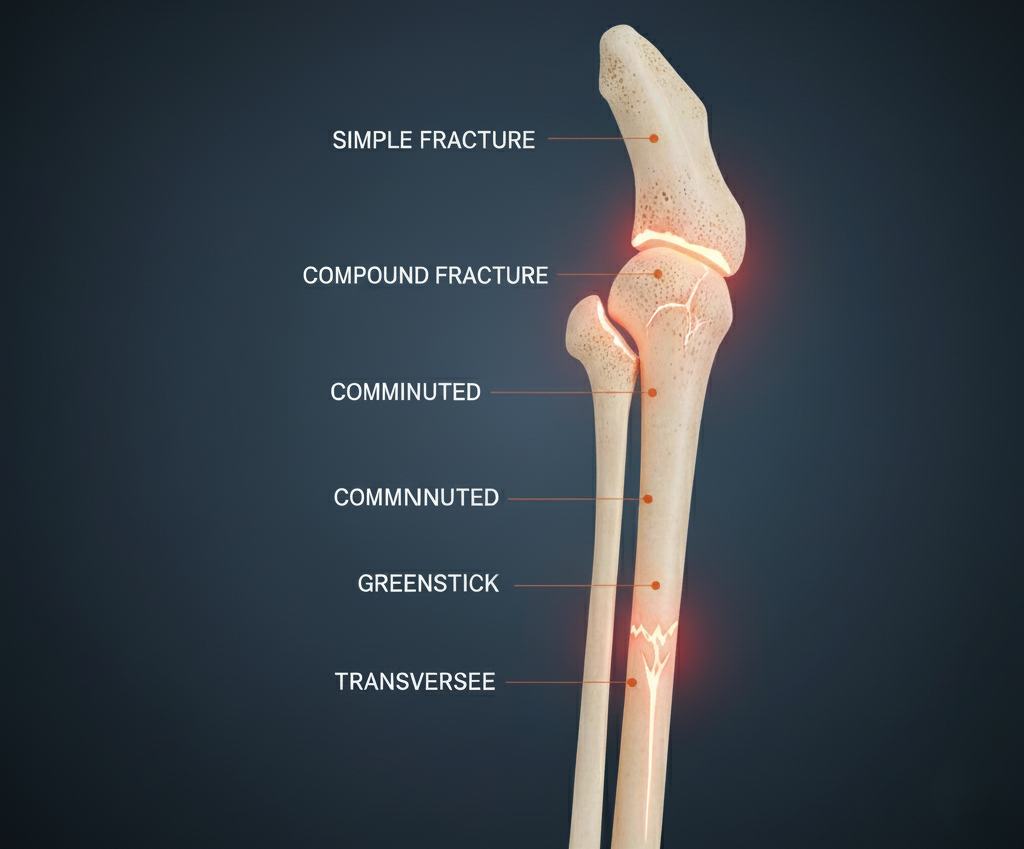

Bone Fractures For the Types, Symptoms, and Effective Treatments

Bone fractures are the breaking of bones or the cracking of bones due to trauma,…